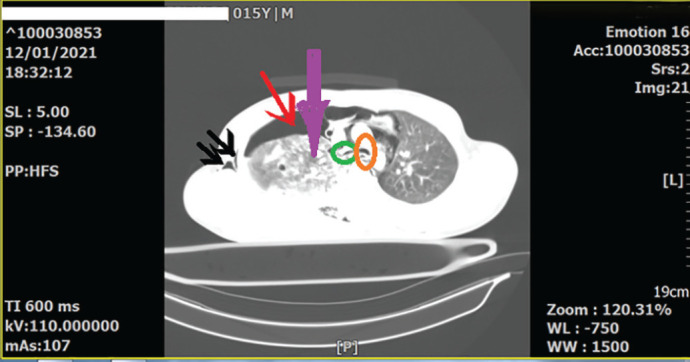

Bronchial rupture following major blunt chest trauma should be suspected in any case of massive and persistent air leak through the intercostal drain tube. Chest radiographs and chest computed tomography scans (CT scans) are highly suggestive of this extremely rare tracheobronchial injury. The present study reported a patient who was a 15-year-old boy. He was a case of a motor-car accident and was brought to the emergency room (ER) of Rajaie Hospital ( Shiraz, Iran) due to dyspnea and chest pain. The physical examination revealed a few crash injuries on his upper extremities, as well as subcutaneous emphysema in his neck. The chest X-ray revealed a right clavicular fracture, multiple rib fractures, a right pneumothorax (but no complete collapse or fallen lung), and also pneumo-mediastinum and subcutaneous emphysema. The chest CT revealed severe pulmonary contusion, severe right-sided pneumothorax, significant pneumo-mediastinum, subcutaneous emphysema, multiple right-side rib fractures, and mild displacement of the right main bronchus. Furthermore, no definitive signs of bronchial rupture were detected. Using a mechanical ventilator, the following parameters were revealed. The maximum pressure (Pmax)=7cm, H2o (was very low), plateau pressure (P. Plateau), and expiratory tidal volume (TV) were not detected due to insufficient amounts. Additionally, increasing TV did not change those values. Bronchial rupture is one of the most important and serious differential diagnoses in forceful chest traumas when the mechanical ventilator reveals low Pmax, very low P.platue, and expiratory TV, with no change in those values with increasing TV.